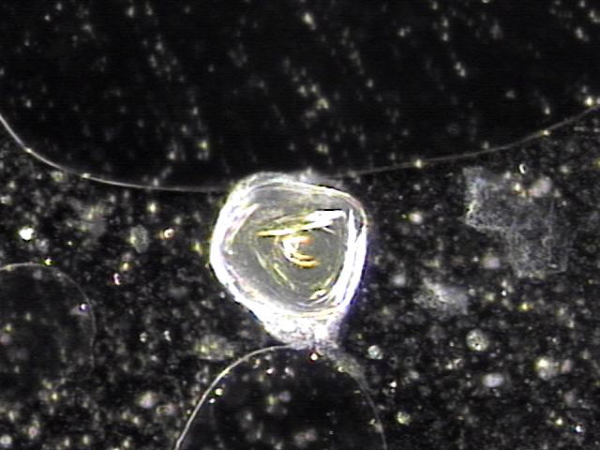

주 2회 전립선의 표적 치료중 전립선액과 정낭액 그리고 전립선 결석과 정관등에 침범하여 퍼지고 있는 균의 배양과 항생제 민감도 검사를 하기위해 표적 치료후 배출된 전립선액의 현미경 검사 자료입니다.

탈락된 상피세포 덩어리와 혈정액과 전립선 결석과 전립선암의 전암병변 의심되는 자료입니다.

This is a microscopic examination of prostatic fluid discharged during biweekly targeted prostate therapy. The sample was obtained to conduct bacterial culture and antibiotic sensitivity testing for organisms invading and spreading through the prostatic fluid, seminal vesicle fluid, prostate calculi, and vas deferens. The findings include clusters of desquamated epithelial cells, hematospermia, prostatic calculi, and features suspicious for precancerous lesions of prostate cancer.